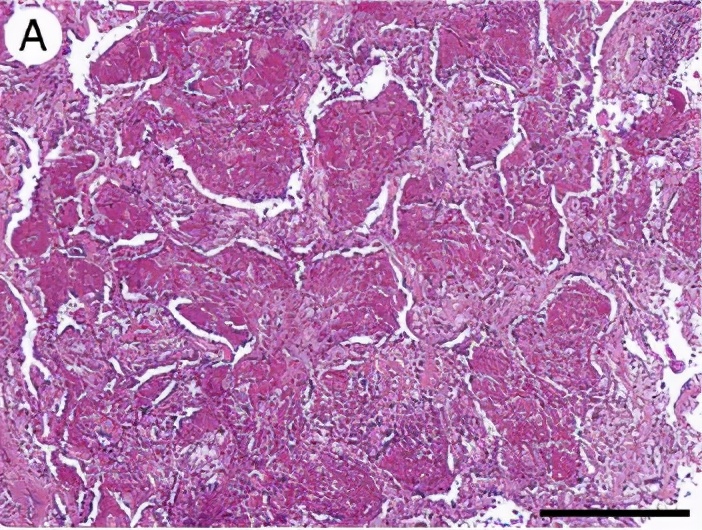

3、慢性过敏性肺炎

慢性HP的诊断更加困难,往往是长期暴露于低浓度抗原或急性反复发作,产生慢性进行性肺损害,呈不可逆肺纤维化。隐匿起病,咳嗽、咳痰、进行性活动时呼吸困难、疲劳,体重减轻。杵状指,散在吸气时爆裂音。晚期可出现呼吸衰竭,肺心病体征。抗原暴露16年(3-40y),诊断延迟达16年。

胸部CT:不规则索条影、网格、结节(小叶中心)、磨玻璃;肺结构改变更明显,支气管扩张,蜂窝肺;肺皱缩(上叶)下叶代偿性肺气肿,但是无钙化和空洞;马赛克(主要见于亚急性/慢性);支气管血管束增重。

过敏性肺炎实际上是吸入抗原诱发的肺脏免疫炎性疾病,临床表现急、亚急性和慢性过程,以亚急性和慢性多见。目前倾向于按是否有纤维化进行分型,非纤维化型HP多指急性/亚急性,HRCT主要是小叶中心结节、斑片磨玻璃影、马赛克征。纤维化型多指慢性HP,HRCT还可见小叶间隔增厚,不规则粗、细网格,伴牵拉支扩,蜂窝等。病理特点为细支气管炎、不同类型不同程度的间质性肺炎(NSIP、OP、UIP)、肉芽肿。BALF:淋巴细胞增多,>40%。诊断主要是依据抗原及与疾病关系、HRCT、BAL-Lym↑。治疗为脱离抗原,酌情激素治疗。过敏性肺炎是一种可防可治的ILD,所以我们要提高认识,积极防诊治,改善病人生活质量。